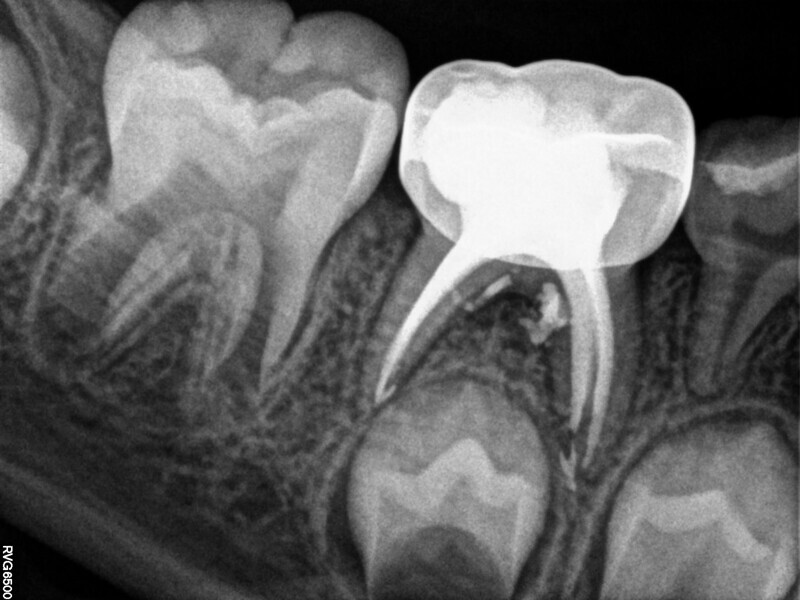

Cas 1 (Figs 1-4)

Cette patiente âgée de 4 ans et 7 mois présentait une douleur qui affectait la seconde molaire temporaire inférieure droite depuis plusieurs jours. L’examen clinique a révélé un gonflement du versant vestibulaire de la gencive et un œdème facial, ainsi qu’une carie occlusale profonde.Un diagnostic de nécrose pulpaire et d’abcès apical symptomatique ayant été posé, un traitement a été prescrit à la patiente, afin de maîtriser l’infection aiguë, et un nouveau rendez-vous a été fixé après l’antibiothérapie. Lors du deuxième rendez-vous, elle ne présentait plus aucune douleur et l’abcès buccal s’était partiellement résorbé. Il a été décidé de procéder à une pulpectomie et à la restauration de la dent. Dans ce cas, la dent présentait une extrusion excessive de matériau d’obturation. Après 15 mois, la réévaluation a confirmé l’absence de signes cliniques ou radiologiques pathologiques, et une apposition osseuse était visible dans la zone de la furcation.